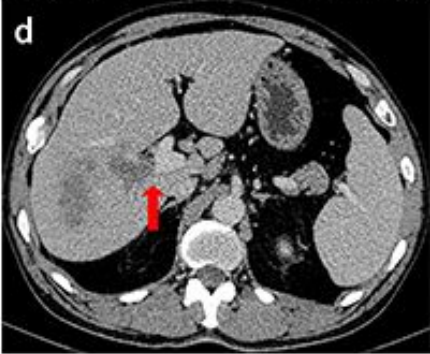

2021年4月22日上腹部增强CT显示:右肝叶肿物较术前减少,最大横截面109mm×85mm(图c)门静脉低密度充血缺损缩小,局限于门静脉右支(图d)。